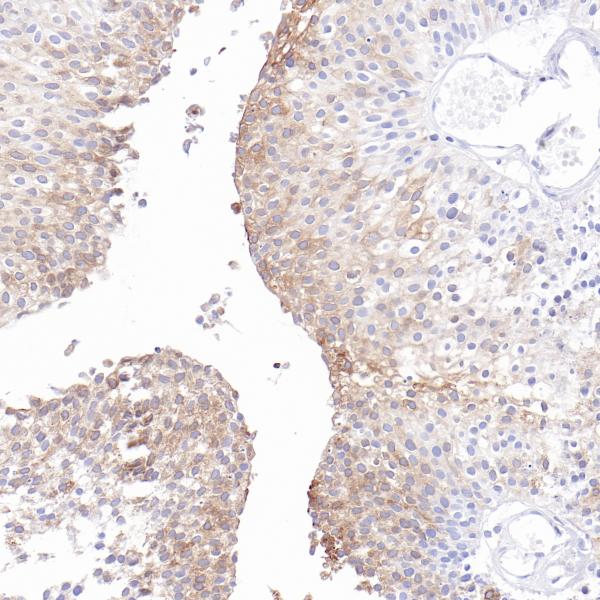

Uroplakin 1a

BP6293

Uroplakin 1b (UPK1B)

BP6310

Uroplakin II

BP6308

Uroplakin III

BP6199